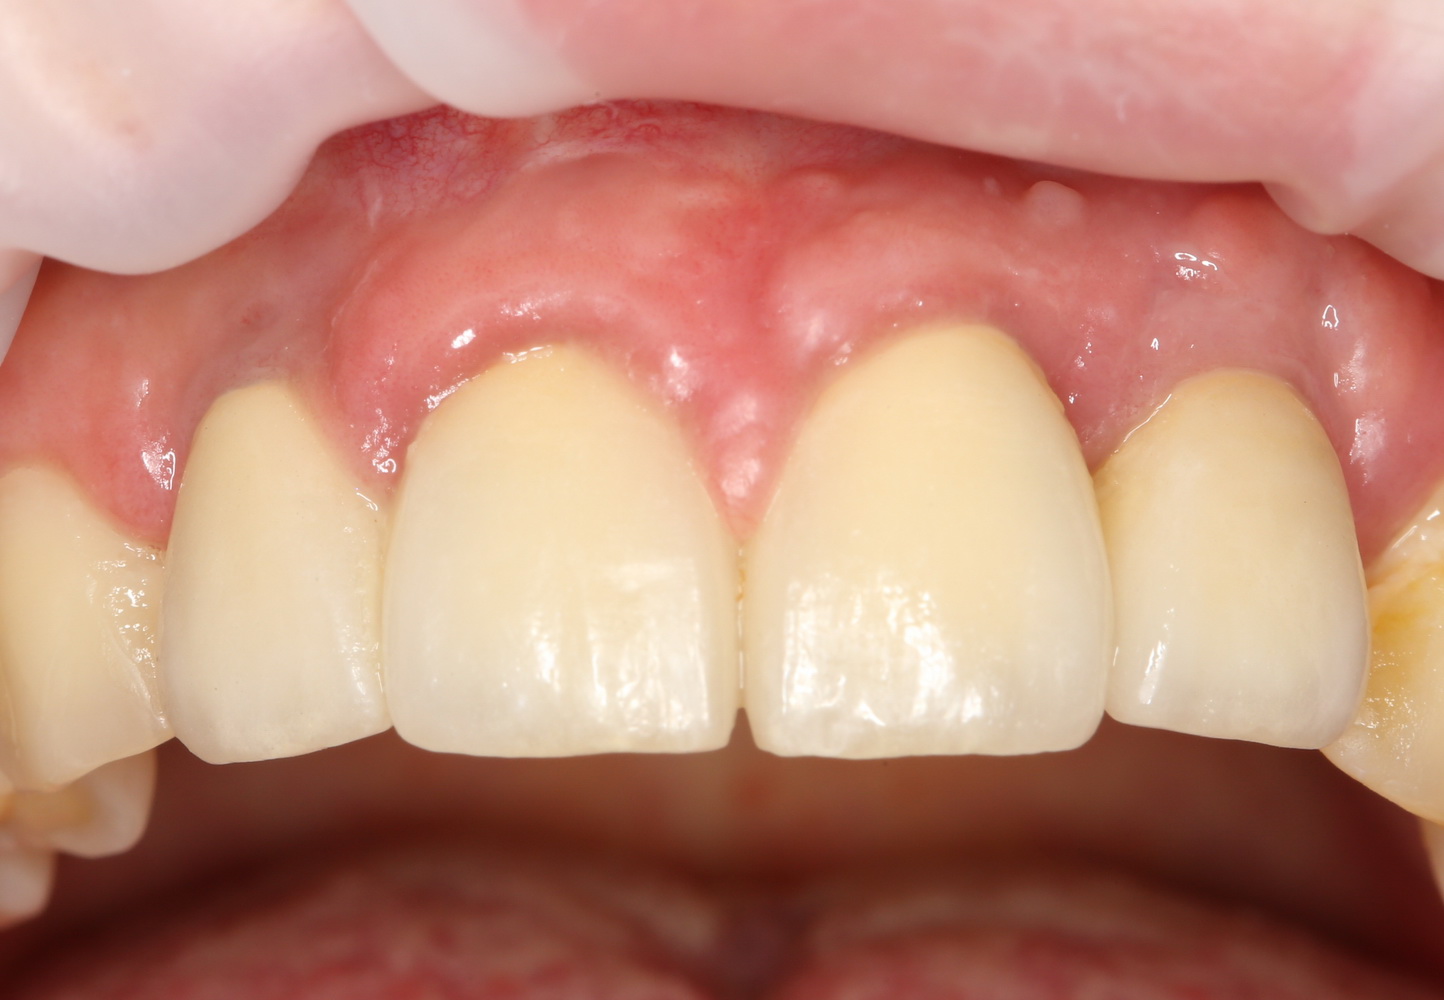

Через три месяца мы сняли коронки с имплантатов, чтобы оценить качество формирования десневого контура:

С этого момента можно перестать переживать — десневой контур сформировался правильно, мы получили достаточный объём и качество окружающей платформу имплантата десны. Можно приступать к изготовлению постоянной протетики. Подрядчиком стала зуботехническая лаборатория French Creative, одна из топовых лабораторий Москвы.

И вот, в жизни Марии наступил долгожданный день — окончательная фиксация керамических коронок на установленные имплантаты:

При этом, она ни дня не оставалась без зубов, была полностью социализирована и жила обычной жизнью. Спустя 5 месяцев после удаления, поставленную Марией клиническую задачу можно считать решёной. Но это с её точки зрения. С нашей же, всё самое интересное только начинается.

Вот клиническая картина и рентгенологический контроль через 2,5 года после имплантации и протезирования: